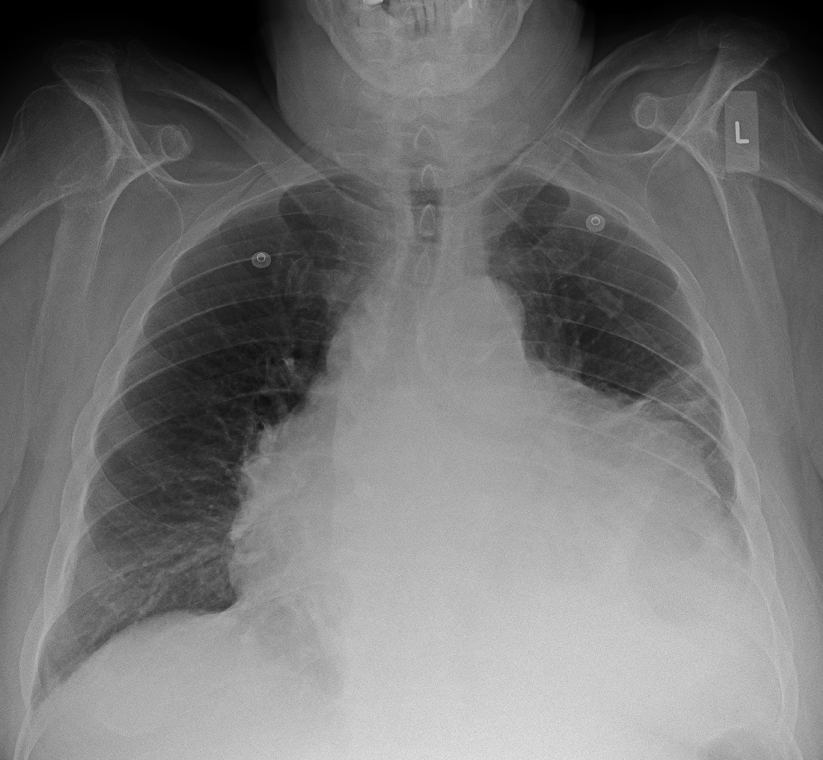

Pericardial effusion

The above chest x-ray shows a huge pericardial effusion. A pericardial effusion is a condition where the sac surrounding the heart (the pericardium) fills up with fluid, like a water balloon. The heart can actually swing around inside of this huge sac of fluid, as shown in this gif (which was created using ultrasound, not x-ray):

Pericardial effusions can be caused by infections (e.g. tuberculosis or coxsackie virus), certain drugs, and inflammatory disorders like lupus.

If a pericardial effusion becomes too severe, it can actually prevent the heart from pumping blood due to the extremely high pressures of the fluid around the heart. This is dangerous and has to be treated immediately by draining away the fluid.